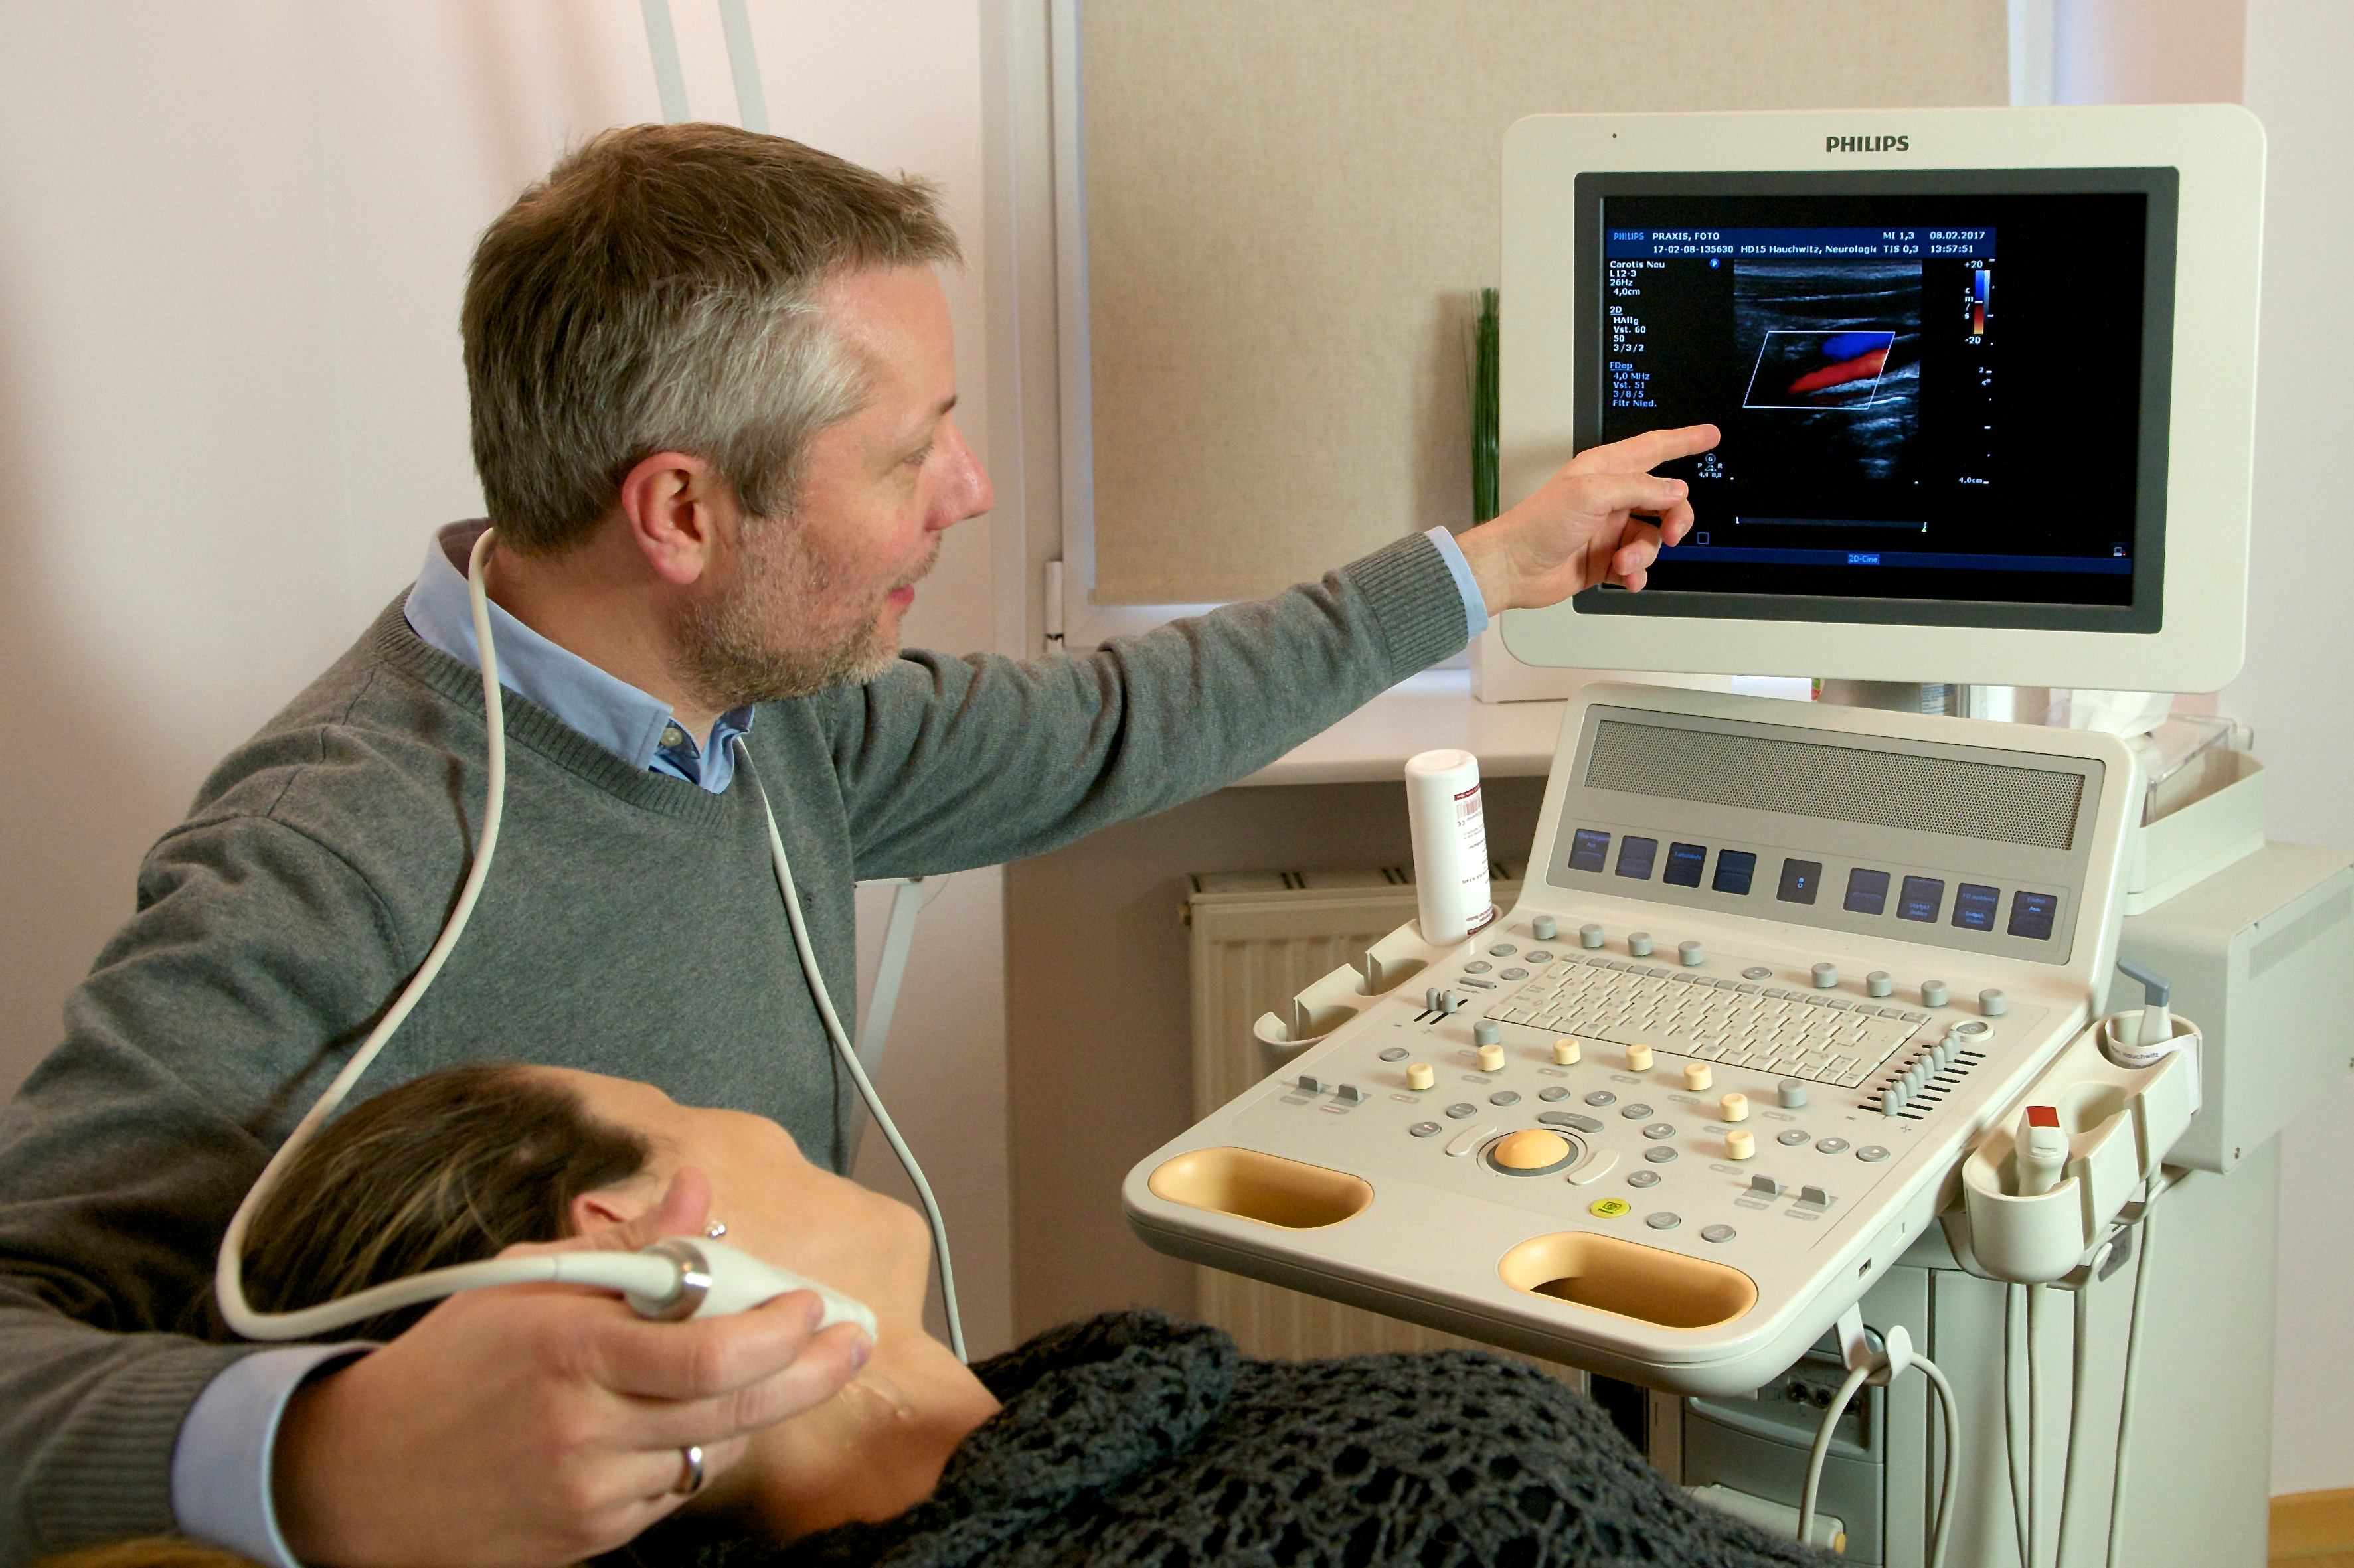

Marc Hauchwitz – Neurologian erikoislääkäri

Saksalaista perusteellisuutta, lämmin ja sympaattinen kohtaaminen.